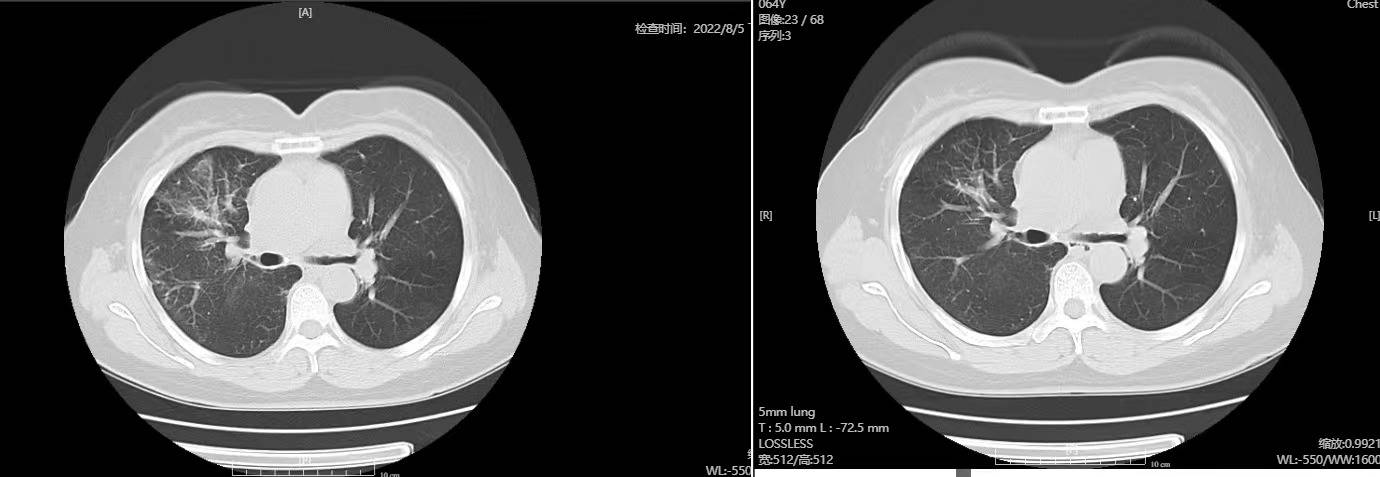

(左边8月,右边7月)

癌性淋巴管炎真的是,太难了。